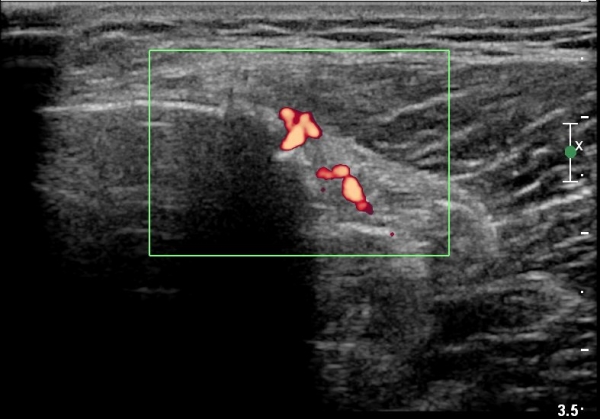

[¹«¸­] °æ°ñ ÇǷΰñÀý ÃÊÀ½ÆÄ¼Ò°ß(sonographic findings of stress fracture of tibia)

¿ìÃø ¹ß¸ñ°ú ¾Æ·§´Ù¸® ÅëÁõ(±â°£ 2ÁÖ)

±º´ë¿¡ ÀÔ´ëÇÏ¿© ÈÆ·ÃÀ» ¹ÞÀº º´·ÂÀÌ Àִ ȯÀÚ´Â ¾à 2ÁÖ ÀüºÎÅÍ ¹ß¸ñ ºÎÀ§ÀÇ ÅëÁõÀÌ ÀÖ´ø Áß

ÃÖ±Ù¿¡´Â ¹ß¸ñ À§ ¾Æ·§´Ù¸®¿¡ ÅëÁõÀÌ ¹ß»ýÇÏ°í ½ÉÇÏ°Ô °ÉÀ¸¸é ½ÉÇØÁö´Â ¾ç»óÀÓ

¾Æ·§´Ù¸® Áß°£ ºÎÀ§¿¡ °æ¹ÌÇÑ ¿¬ºÎÁ¶Á÷ ºÎÁ¾ÀÌ °üÂûµÇ°í ¾à°£ÀÇ ±¹¼ÒÀû ¾ÐÅëÀ» º¸ÀÓ.

ÃÊÀ½ÆÄ °Ë»ç

¹Ì¼¼ÇÏ°Ô ¿¬ºÎÁ¶Á÷ ºÎÁ¾°ú °¡°ñ Çü¼ºÀÌ °üÂûµÊ.

Bilateral stress fracture of the tibia diagnosed by ultrasound. A case report

https://www.ncbi.nlm.nih.gov/pmc/articles/PMC3558228/pdf/main.pdf